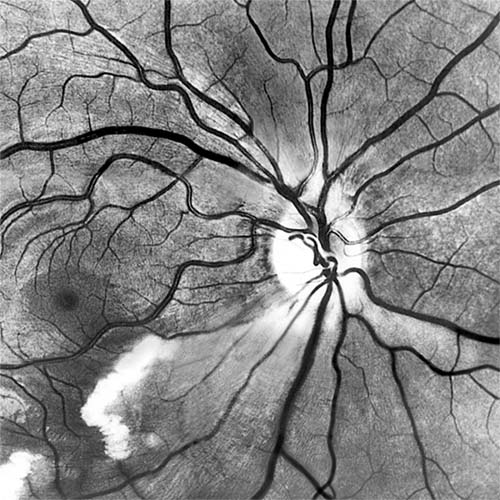

Red-free light (a white light with a green filter) allows details of hemorrhages, focal irregularity of blood vessels, and nerve fibers to be seen more clearly (Figure 15-9).

Figure 15-9

Figure 15-9: Acute retinal infarction. Red-free photograph shows acute arterial occlusion in a congenitally anomalous vessel at the disk. The inferior retina is infarcted, but axoplasm has accumulated beneath the fovea in an irregular pattern owing to preserved neuronal function of the distal ganglion cells.